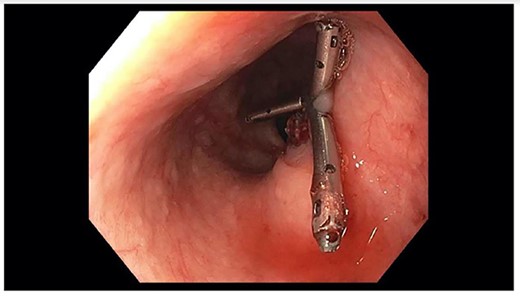

A 71-year-old male with past medical history of type 2 diabetes and hypertension presented to the emergency department at St. Joseph’s University Medical Center with severe respiratory distress. On nonrebreather, the patient’s oxygen saturation was 49%. The patient was subsequently intubated. Evaluation revealed pneumonia secondary to COVID-19 leading patient to be intubated on ventilator support for 4 weeks. During this time patient was maintained on enteral feeding through nasogastric tube, and was on gastrointestinal prophylaxis Protonix 40 mg daily for the duration of his admission. Ultimately, the patient made full recovery and was sent home; however, approximately 3 weeks later, he presented to the emergency department due to syncope. The patient experienced large-volume bright red hematemesis. He became hypotensive and was transfused three units of packed red blood cells and started on pressors. The patient was intubated and transferred to the intensive care unit (ICU) with acute blood loss anemia and hypovolemic shock. Here, an esophagogastroduodenoscopy (EGD) was performed revealing midesophageal bleed (Fig. 1). Hemostasis was achieved with clipping; however, post-procedurally, the patient again became hypotensive. Repeat EGD showed a nonbleeding esophageal ulcer with three clips in good position (Fig. 2). Computed tomography (CT) angiogram of the thorax was performed revealing an actively bleeding aberrant right subclavian artery perforating into the esophagus (Figs 3 and 4). The right subclavian artery was noted to be of normal caliber without ectasia or aneurism and the esophagus was free of any other pathology. Thoracic and vascular surgery were consulted; however, the bleed was deemed of nonsurvivable pathology due to comorbidities and current clinical status. Ultimately, the family of the patient decided to withdraw care and the patient passed.

Repeat EGD showing three clips from prior EGD; no evidence of active bleeding.